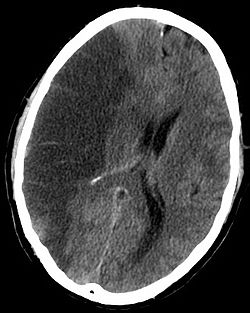

- Moždani udar, cerebrovaskularni insult

označava prestanak funkcionisanja određenih grupa moždanih ćelija

(oštećenje moždanog parenhima), a nastaje usljed nedostatka

hranljivih materija i/ili kisika. Nedostatak ovih materija se javlja

kao posljedica poremećaja krvotoka usljed začepljenja krvnih sudova

ili usljed njihovog prskanja i izliva krvi u moždano tkivo ili

moždane ovojnice

| CT snimak

mozga za vrijeme mozdanog udara |